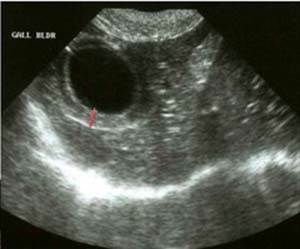

Холецистит у кошек не имеет определенных специфических клинических признаков, поэтому для установления диагноза необходим общий и биохимический анализы крови, анализ мочи, ультразвуковое исследование печени и желчного пузыря. В случае образования камней в желчном пузыре они могут быть видны на рентгенограмме брюшной полости. При выявлении изменения стенки желчного пузыря и неоднородности желчи при ультразвуковом исследовании рекомендуется тонкоигольная биопсия желчного пузыря с последующим цитологическим и микробиологическим исследованием полученной желчи.